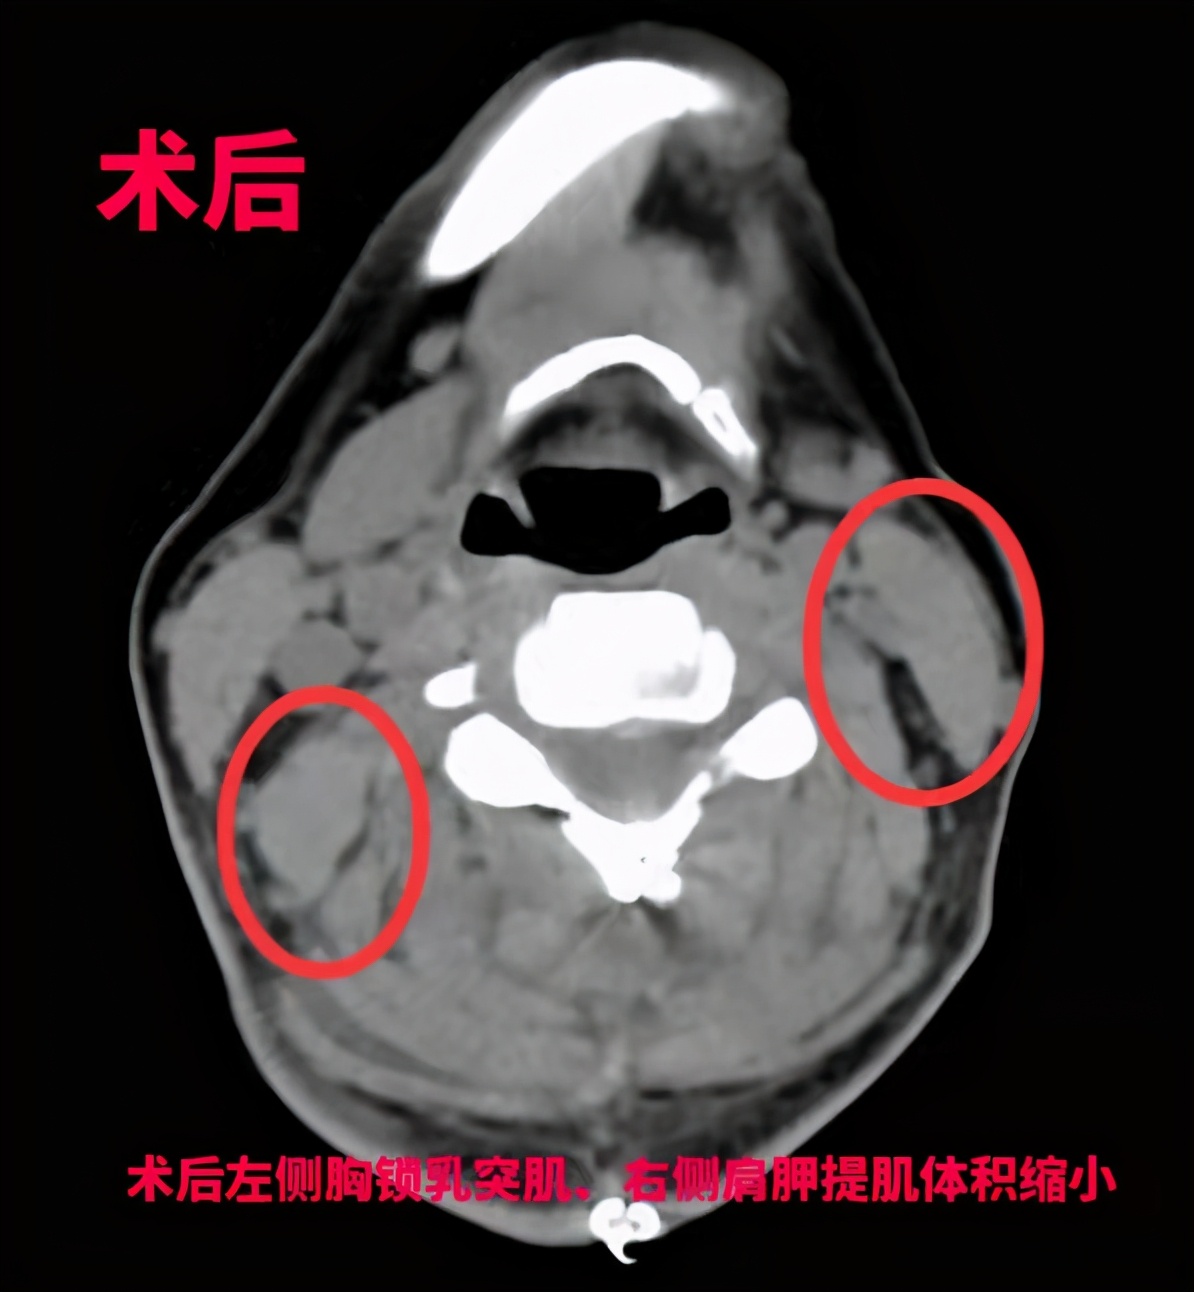

“最好的方式是手术,考虑到钟女士年轻还要负担一家老小,我们决定选择用‘超选择性神经根切断术’治疗她的痉挛性斜颈。”王向宇表示,相比于其他方式,这种术式需要在术前进行详细检查和评估,通过影像、肌电图检查、选择性肌肉阻滞等专业方法,事先找到“肇事”肌肉,在术中用最小电量反复刺激,精准找到这些“肇事”肌肉的支配神经,进行选择性的神经根切断,而不伤害其他神经和肌肉,进一步减少损伤。经过6个小时后,手术宣布成功,钟女士经过1周的恢复,“歪脖子”的问题得到了根本性解决。

王向宇表示,“超选择性神经根切断术”的优点就在“超选择性”上。手术方式可以做到仅切断参与痉挛性斜颈肌肉的支配神经,不多切也不少切。而与DBS手术相比,超选择性神经根切断术,大部分费用属于医保可以报销额范围,普通患者家庭无须太多的顾虑手术费用的问题。